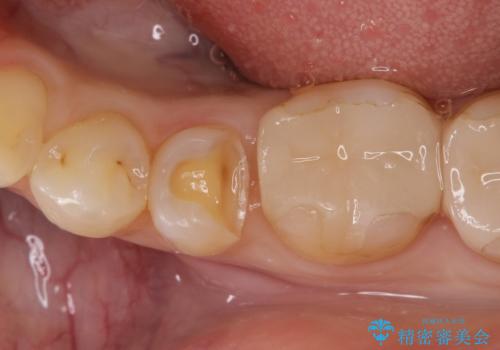

虫歯の治療(セラミックインレー)

- 定期検診にて虫歯が見つかり、セラミックインレーに治療を行っております。

e-max プレスインレーにて修復治療を行っているため適合性及び審美性の高い治療を行うことができます